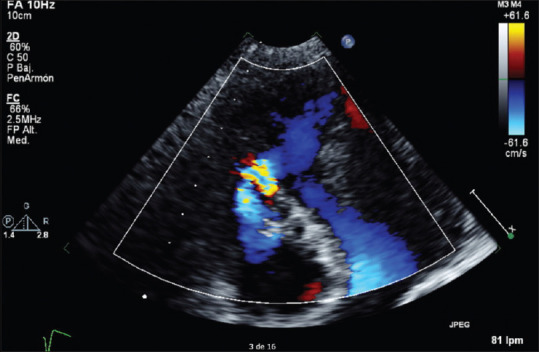

Masquerading bundle branch block (MBBB) is a rare presentation of bifascicular blocks. It is the result of a right bundle branch block associated with an advanced left anterior fascicular block due to extensive damage to the conduction system. We present the case of a 75-year-old male with late onset presentation anterior wall myocardial infarction (MI) with ongoing ischemia (which evolved into a ventricular septal defect [VSD]). Electrocardiographically, the MBBB is characterized by a prominent R in V1, left axis deviation and absence of small S waves in I and aVL. Its presence confers a poor prognosis and high risk of progressing to advanced atrioventricular block (AAVB). A mortality rate between 18% and 38.9% has been found and 41.4%-59% of the patients develop AAVB requiring pacemaker implantation. To our knowledge, this is the first reported MBBB case in the setting of an MI complicated with VSD, demonstrating its association with the presence of critical anteroseptal ischemia. The patient rejected any kind of intervention, palliative care was offered, and he died 2 months later.

伪装束支阻滞(MBBB)是一种罕见的双束状阻滞。它是由于传导系统的广泛损伤而导致的右束支阻滞合并晚期左前束阻滞的结果。我们报告一例75岁男性迟发性前壁心肌梗死(MI)伴持续缺血(演变为室间隔缺损[VSD])。在心电图上,MBBB的特征是V1明显的R,左轴偏移,I和aVL没有小S波。它的存在导致预后不良和进展为晚期房室传导阻滞(AAVB)的高风险。死亡率在18% - 38.9%之间,41.4%-59%的患者发生AAVB,需要植入起搏器。据我们所知,这是第一例心肌梗死合并室间隔缺损的MBBB病例,表明其与严重室间隔缺血存在关联。患者拒绝任何干预,接受姑息治疗,2个月后死亡。